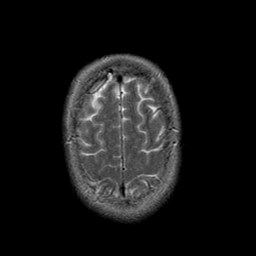

Stroke:T2-weighted MR #1 -- Slice #21

[Home][Help][Clinical] Slice 21